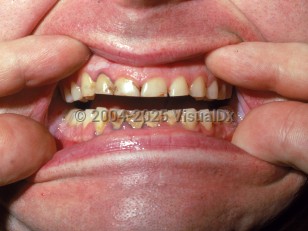

Arsenic poisoningArsenic poisoning

Lead poisoningLead poisoning